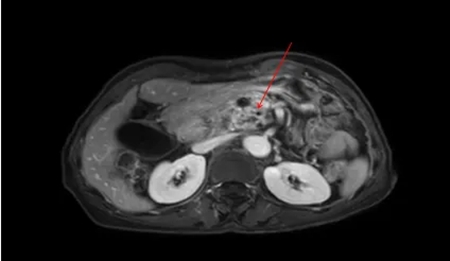

入院后,腹部增强CT、胰腺MRI、PET/CT等检查纷纷指向胰腺病变。一场针对疑难胰腺病例的多学科大会诊(MDT) 迅速启动!在刘谦主任主持下,医学影像科郭辉主任、放疗科巴楠主任、肿瘤科张剑主任、肝胆胰腺外科张永医师、营养科丁丽敏主任共同参与“会诊”。

▲ 胰腺增强MRT:胰头钩突占位,可见多发小囊状,胰管扩张